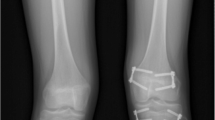

Patients were placed supine on a standard flat top radiolucent table. Biplane fluoroscopy was used with two C-arms to obtain simultaneous anteroposterior and lateral images of the knee to mitigate accurate screw placement. The entire limb was prepared and draped from the groin to the foot. Fluoroscopy was used to locate the sites for the skin incisions to achieve the most accurate screw trajectory. Screws were inserted in a parallel or crossed fashion according to surgeon preference. When parallel screws were used, on the medial side a guide pin was inserted through a 1-cm incision aiming to cross the physis at the junction of the medial and central one-third in the coronal plane and in the middle one-third of the physis in the sagittal plane. Similarly, on the lateral side a guide pin was inserted through a 1-cm incision aiming to cross the physis at the junction of the lateral and central one-third in the coronal plane and in the middle one-third of the physis in the sagittal plane (Fig. 1). When crossed screws were used, on the medial side a guide pin was inserted through a 1-cm incision aiming to cross the physis at the junction of the lateral and central one-third in the coronal plane and in the middle one-third of the physis in the sagittal plane. Similarly, on the lateral side a guide pin was inserted through a 1-cm incision aiming to cross the physis at the junction of the medial and central one-third in the coronal plane and in the middle one-third of the physis in the sagittal plane (Fig. 2). The guide pins stopped just short of the articular surface and a depth gauge was used to determine screw length. After drilling through the outer cortex under fluoroscopic guidance, 7.3-mm cannulated screws with a 32-mm thread were placed over the guide pins stopping just short of the articular surface. The skin incisions were closed with subcuticular absorbable sutures and covered with a sterile dressing. One patient had parallel screws placed in the distal femur, 12 patients had parallel screws placed in the distal femur and proximal tibia and 3 patients had crossed screws in the distal femur and proximal tibia.